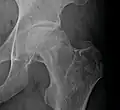

Front X-ray of right knee of an adolescent (epiphyseal plates are open): arrows point to avascular necrosis and developing osteochondritis dissecans in the outer medial condyle of femur

In the early stages, bone scintigraphy and MRI are the preferred diagnostic tools.[18][19]

X-ray images of avascular necrosis in the early stages usually appear normal. In later stages it appears relatively more radio-opaque due to the nearby living bone becoming resorbed secondary to reactive hyperemia.[2] The necrotic bone itself does not show increased radiographic opacity, as dead bone cannot undergo bone resorption which is carried out by living osteoclasts.[2] Late radiographic signs also include a radiolucency area following the collapse of subchondral bone (crescent sign) and ringed regions of radiodensity resulting from saponification and calcification of marrow fat following medullary infarcts.